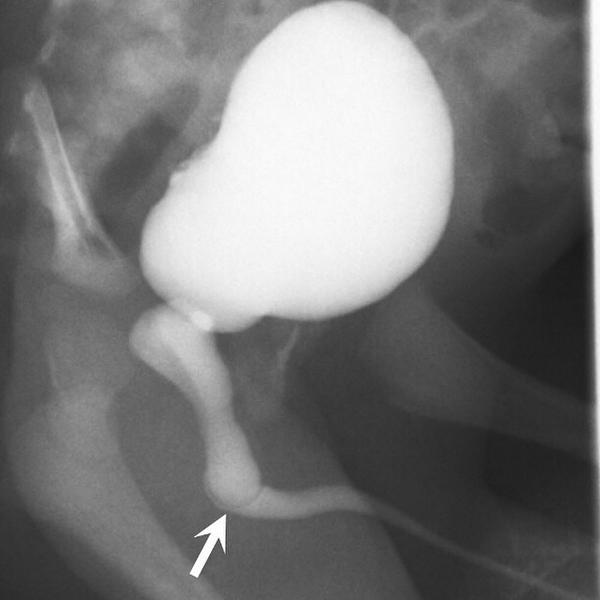

Lateral image from a #voiding #cystourethrogram shows a dilated posterior urethra. There is a curvilinear lucency...